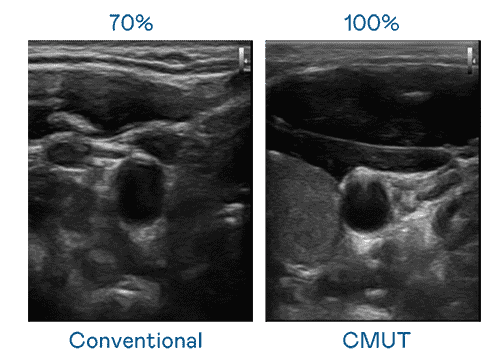

CMUT 技术是一种用电容式微机电元件来产生超音波讯号的技术。。。与传统 PZT 压电式技术相比,,,CMUT 频宽增加 30%,,,更宽频的超音波讯号让影像解析度大幅提升,,,,是实现高影像品质医疗超音波扫描、、促进精准医疗发展的关键技术。。

超音波影像的解析度高低,,,首先取决于探头能发出的讯号频宽。。。。EBpay CMUT 可提供高清晰的超音波讯号,,提供高频宽、、、高灵敏度、、影像纹理细节更高的超音波影像,,,协助医护人员缩短影像判读时间及利用精准的医疗影像进行诊断。。。